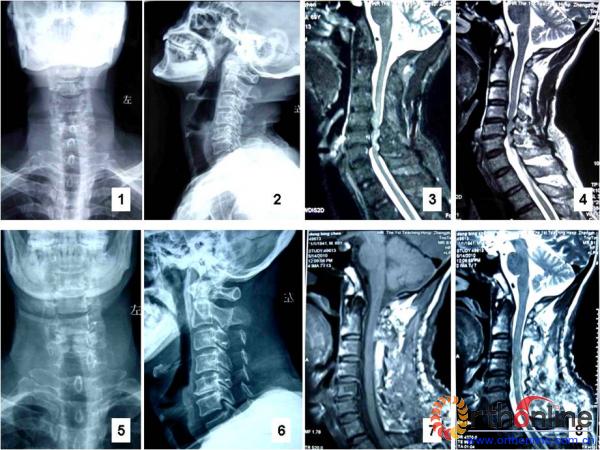

图1 董XX,男,69岁,多节段脊髓型颈椎病。1,2:术前颈椎正侧位X线片;3,4:术前MRI显示,C3-4脊髓前方受压,C6-7脊髓后方受压,C4-5、C5-6为钳夹型,脊髓前后方均严重受压;5,6:术后颈椎正侧位X线片,可见3个锚钉影像;7,8:术后MRI显示,C3-7脊髓前后方压迫获得解除,病人病情明显好转,疗效为优